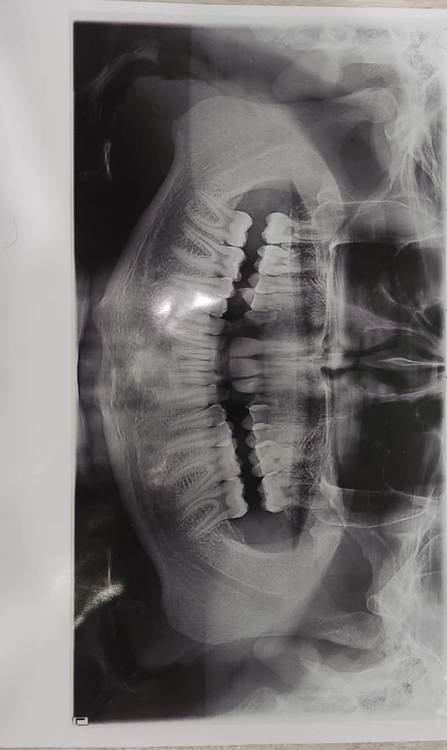

smikvarnik Опубликовано 12 июня, 2023 Поделиться Опубликовано 12 июня, 2023 (изменено) Здравствуйте, проблема следующая 25 лет, пол М У меня с детства аномалии(нет корней на 3х зубах), одна двойка справа молочная + тройки молочные. Двойка выпала и хожу с дыркой уже лет 10, также зона улыбки кривовата и есть промежуток между однерками тройки молочные маленькие но держатся, все хорошо. Самая главная проблема по которой мне многие отказывали в реставрации только зоны улыбки, это прикус. у меня глубокий прикус с детства. Ортодонты говорят что нужно носить брекеты 2-3 года, и только после этого имплантация либо коронки с мостами. Но пару ортопедов предложили мне сточить все верхние зубы(все жевательные зубы в отличном состоянии, передние так себе, уже немного сточены из за прикуса). Говорят что если поставить без исправления прикуса - я просто выбью коронки или импланты, нагрузка будет не такая какая должна быть Пробовал также ходить с капой чтобы поднять прикус - результатов нет. некоторые врачи отказывали даже в лечении брекетами, говоря что ситуация сложная. Также зубы для моего возраста маленькие, по сравнению с другими людьми Говорят что если сделать коронки на верхней челюсти, можно таким образом исправить прикус+сделать улыбку без ортодонтии. но также возможно потребуется сточить немного зубов на нижней(не уточнял какие) Коронки из диоксида циркония как вы считаете, это нормальный вариант, или так себе? у меня психологический комплекс из за зубов и еще 2-3 года ходить с брекетами и дырками честно говоря так себе идея. Какие есть минусы и опасности у такого варианта, и как с вашей точки зрения, как докторов, этот вариант оценивается? Насколько это целесообразно? Спасибо за помощь заранее, очень жду ответ, каждый день волнует эта тема Изменено 12 июня, 2023 пользователем smikvarnik Ссылка на комментарий

smikvarnik Опубликовано 13 июня, 2023 Автор Поделиться Опубликовано 13 июня, 2023 здравствуйте, не видел! исправляю еще также есть фото лица и самих зубов, как попросите так и сфоткаю. также есть КТ ВЧ и НЧ Ссылка на комментарий

smikvarnik Опубликовано 13 июня, 2023 Автор Поделиться Опубликовано 13 июня, 2023 также ситуация во рту, и с прикусом. молочные зубы выделил. извините за флуд) Ссылка на комментарий